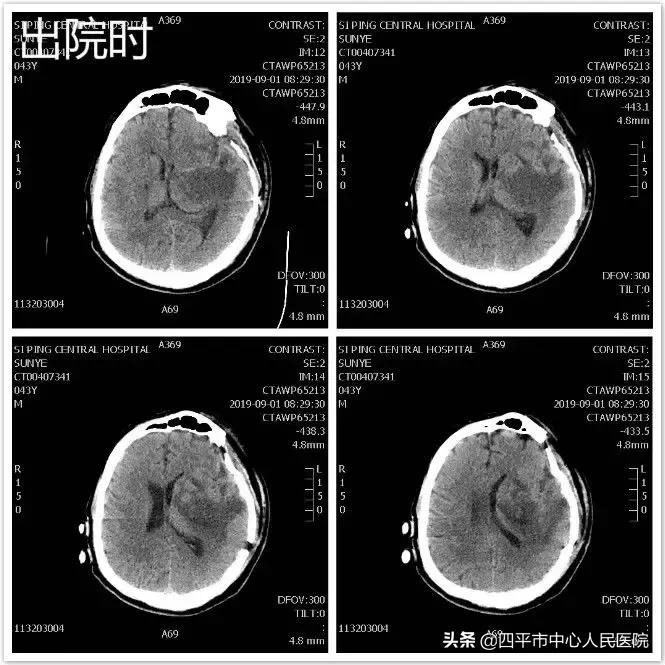

患者孙XX,入院前约21小时无明显诱因突发言语不清伴右侧肢体活动不灵,表现为肢体瘫痪,既往高血压病史约10年,最高可达180mmHg,不规律服用降压药物急被家属送至我院就诊,急送我院急诊给予查头部CT后,示脑出血。患者入院后病情呈进行性加重,患者符合手术指征,行头部CT定位见出血量增加,头部CTA示相当于左侧后交通动脉起始部小动脉瘤,李晓东主任带领马龙医生在清除脑出血的同时将动脉瘤夹闭,出院时,患者病情平稳,预后较好。